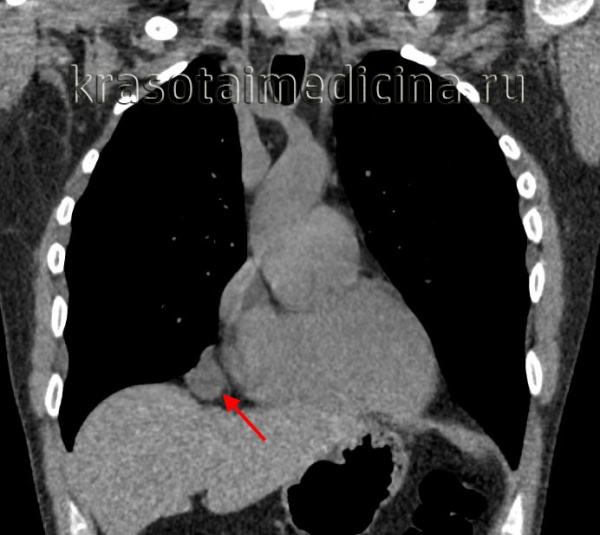

Рентгеновские снимки тератомы средостения: Диагностика и лечение

Раздел: Фотоэссе